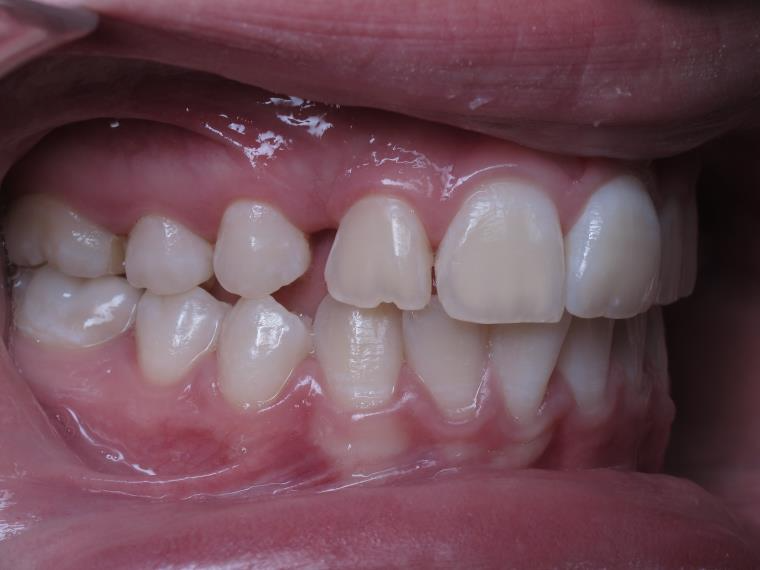

appareillage multibagues pendant 3 ans

surveillance de la dentition par gouttieres nocturne

bilan début et fin de traitement